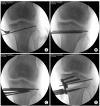

Materials and methods: Fifty-one patients (52 knees) who underwent medial OWHTO from October 2007 to April. 2010 were included in the study. The patients were divided into group I (n=29) that received an autogenous tricortical bone graft and group II (n=23) that received an allogenous cancellous bone chip graft. The radiographic parameters (preoperative anatomical and mechanical femorotibial angles, modified tibial bone varus angle, and posterior tibial slope), clinical parameters, bone union period, and complications were evaluated from medical records.

Results: The radiographic and clinical outcomes did not show significant difference between two groups. The average bone union period was 11.7 weeks in group I and 12.1 weeks in group II. The visual analog scale score on the first postoperative day was significantly higher in group I than group II.